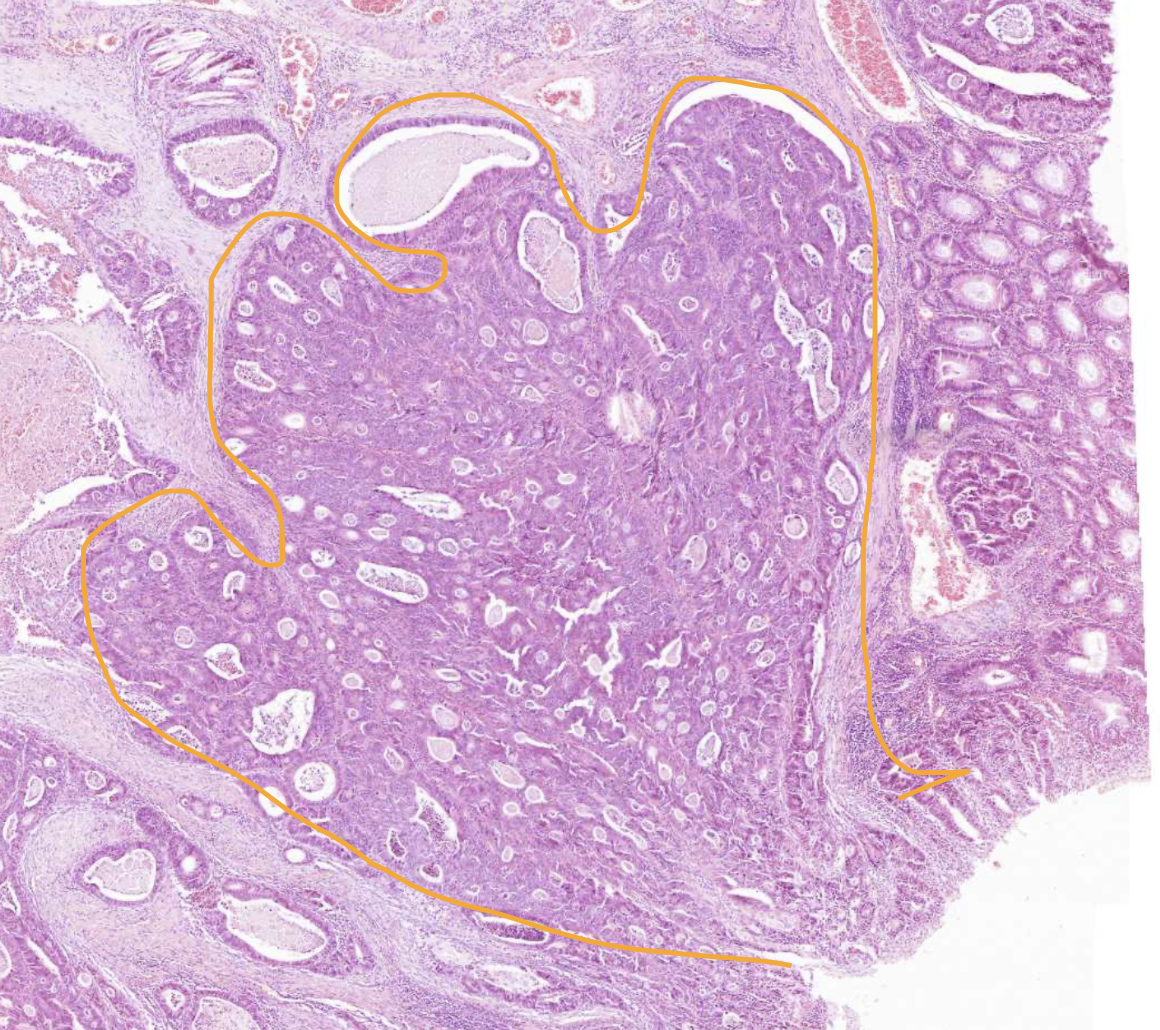

Well differentiated colon adenocarcinoma

Gland-like structures at wrong location in well differentiated colon adenocarcinoma

Different sized, closely bound gland-like tubule/crypts

Cell debris in the lumen of the glands (necrotic cell remains mixed with inflammatory cells ) - can be a sign of relative lability of the cancer cells and/or be caused by ischaemia

No lamina propria between, located very close to each other - Pushed together, not growing in a normal way

Why is all of these images diagnosed as well differentiated colon adenocarcinoma and not poorly differentiated?

Even though there are cancer cells present that are morphologically different from normal, they are still forming some kind of tubular structure (not the normal shape, but still there) → Well differentiated